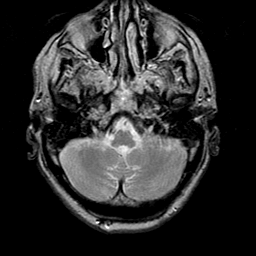

Meningioma, MR Study #1 -- Slice #2

[Home][Help][Clinical] Slice 2